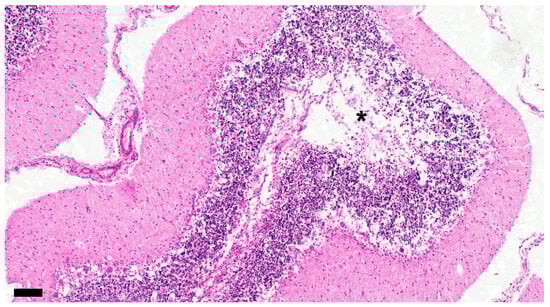

Figure 5. Demyelination is apparent around blood vessel (asterisk) showing cuffing (black arrow). Dog No. 11. Chronic group. LFB. Scale = 90 μm.

LFB staining at each stage is shown in Figure 4a–f, demyelinating changes in white matter are shown in Figure 5, and CDV-immunoreactive particle deposition is shown in Figure 6a–d.

In the chronic group, changes such as severe demyelination, a significant increase in the number and enlargement of astrocytes and microglia, an increase in CDV-immunoreactive particles, and an increase in inclusion bodies were progressing. The perivascular cuffing showed three or more layers.